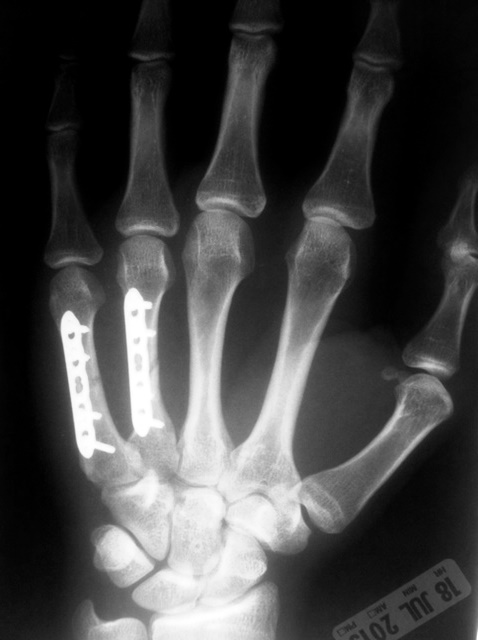

X-rays:

Images below are from a patient with 4th and 5th metacarpal shaft fractures in the hand. The fractures were displaced and unstable, requiring surgery to improve the patient’s hand function. ORIF with plates and screws was performed.